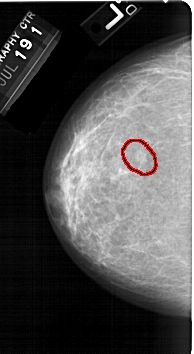

A_1323_1.LEFT_MLO

LEFT_MLO LINES 5491 PIXELS_PER_LINE 3256 BITS_PER_PIXEL 12 RESOLUTION 43.5 OVERLAY

FILE: A_1323_1.LEFT_MLO.OVERLAY

TOTAL_ABNORMALITIES 1

ABNORMALITY 1

LESION_TYPE MASS SHAPE OVAL MARGINS OBSCURED-ILL_DEFINED

ASSESSMENT 4

SUBTLETY 2

PATHOLOGY BENIGN

TOTAL_OUTLINES 1

BOUNDARY